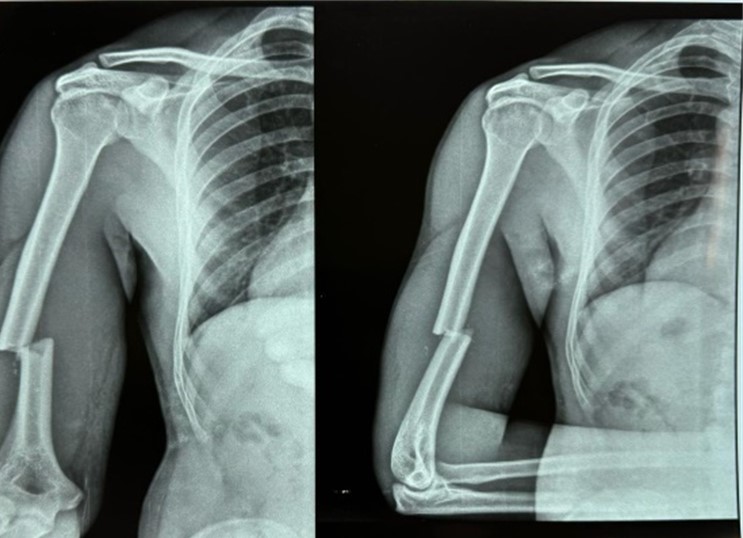

35 year old male patient suffering from closed displaced diaphyseal humerus fracture without distal neurovascular deficit. Follow up was taken at 3months post operatively and 12 months post operatively

Pre operative xray